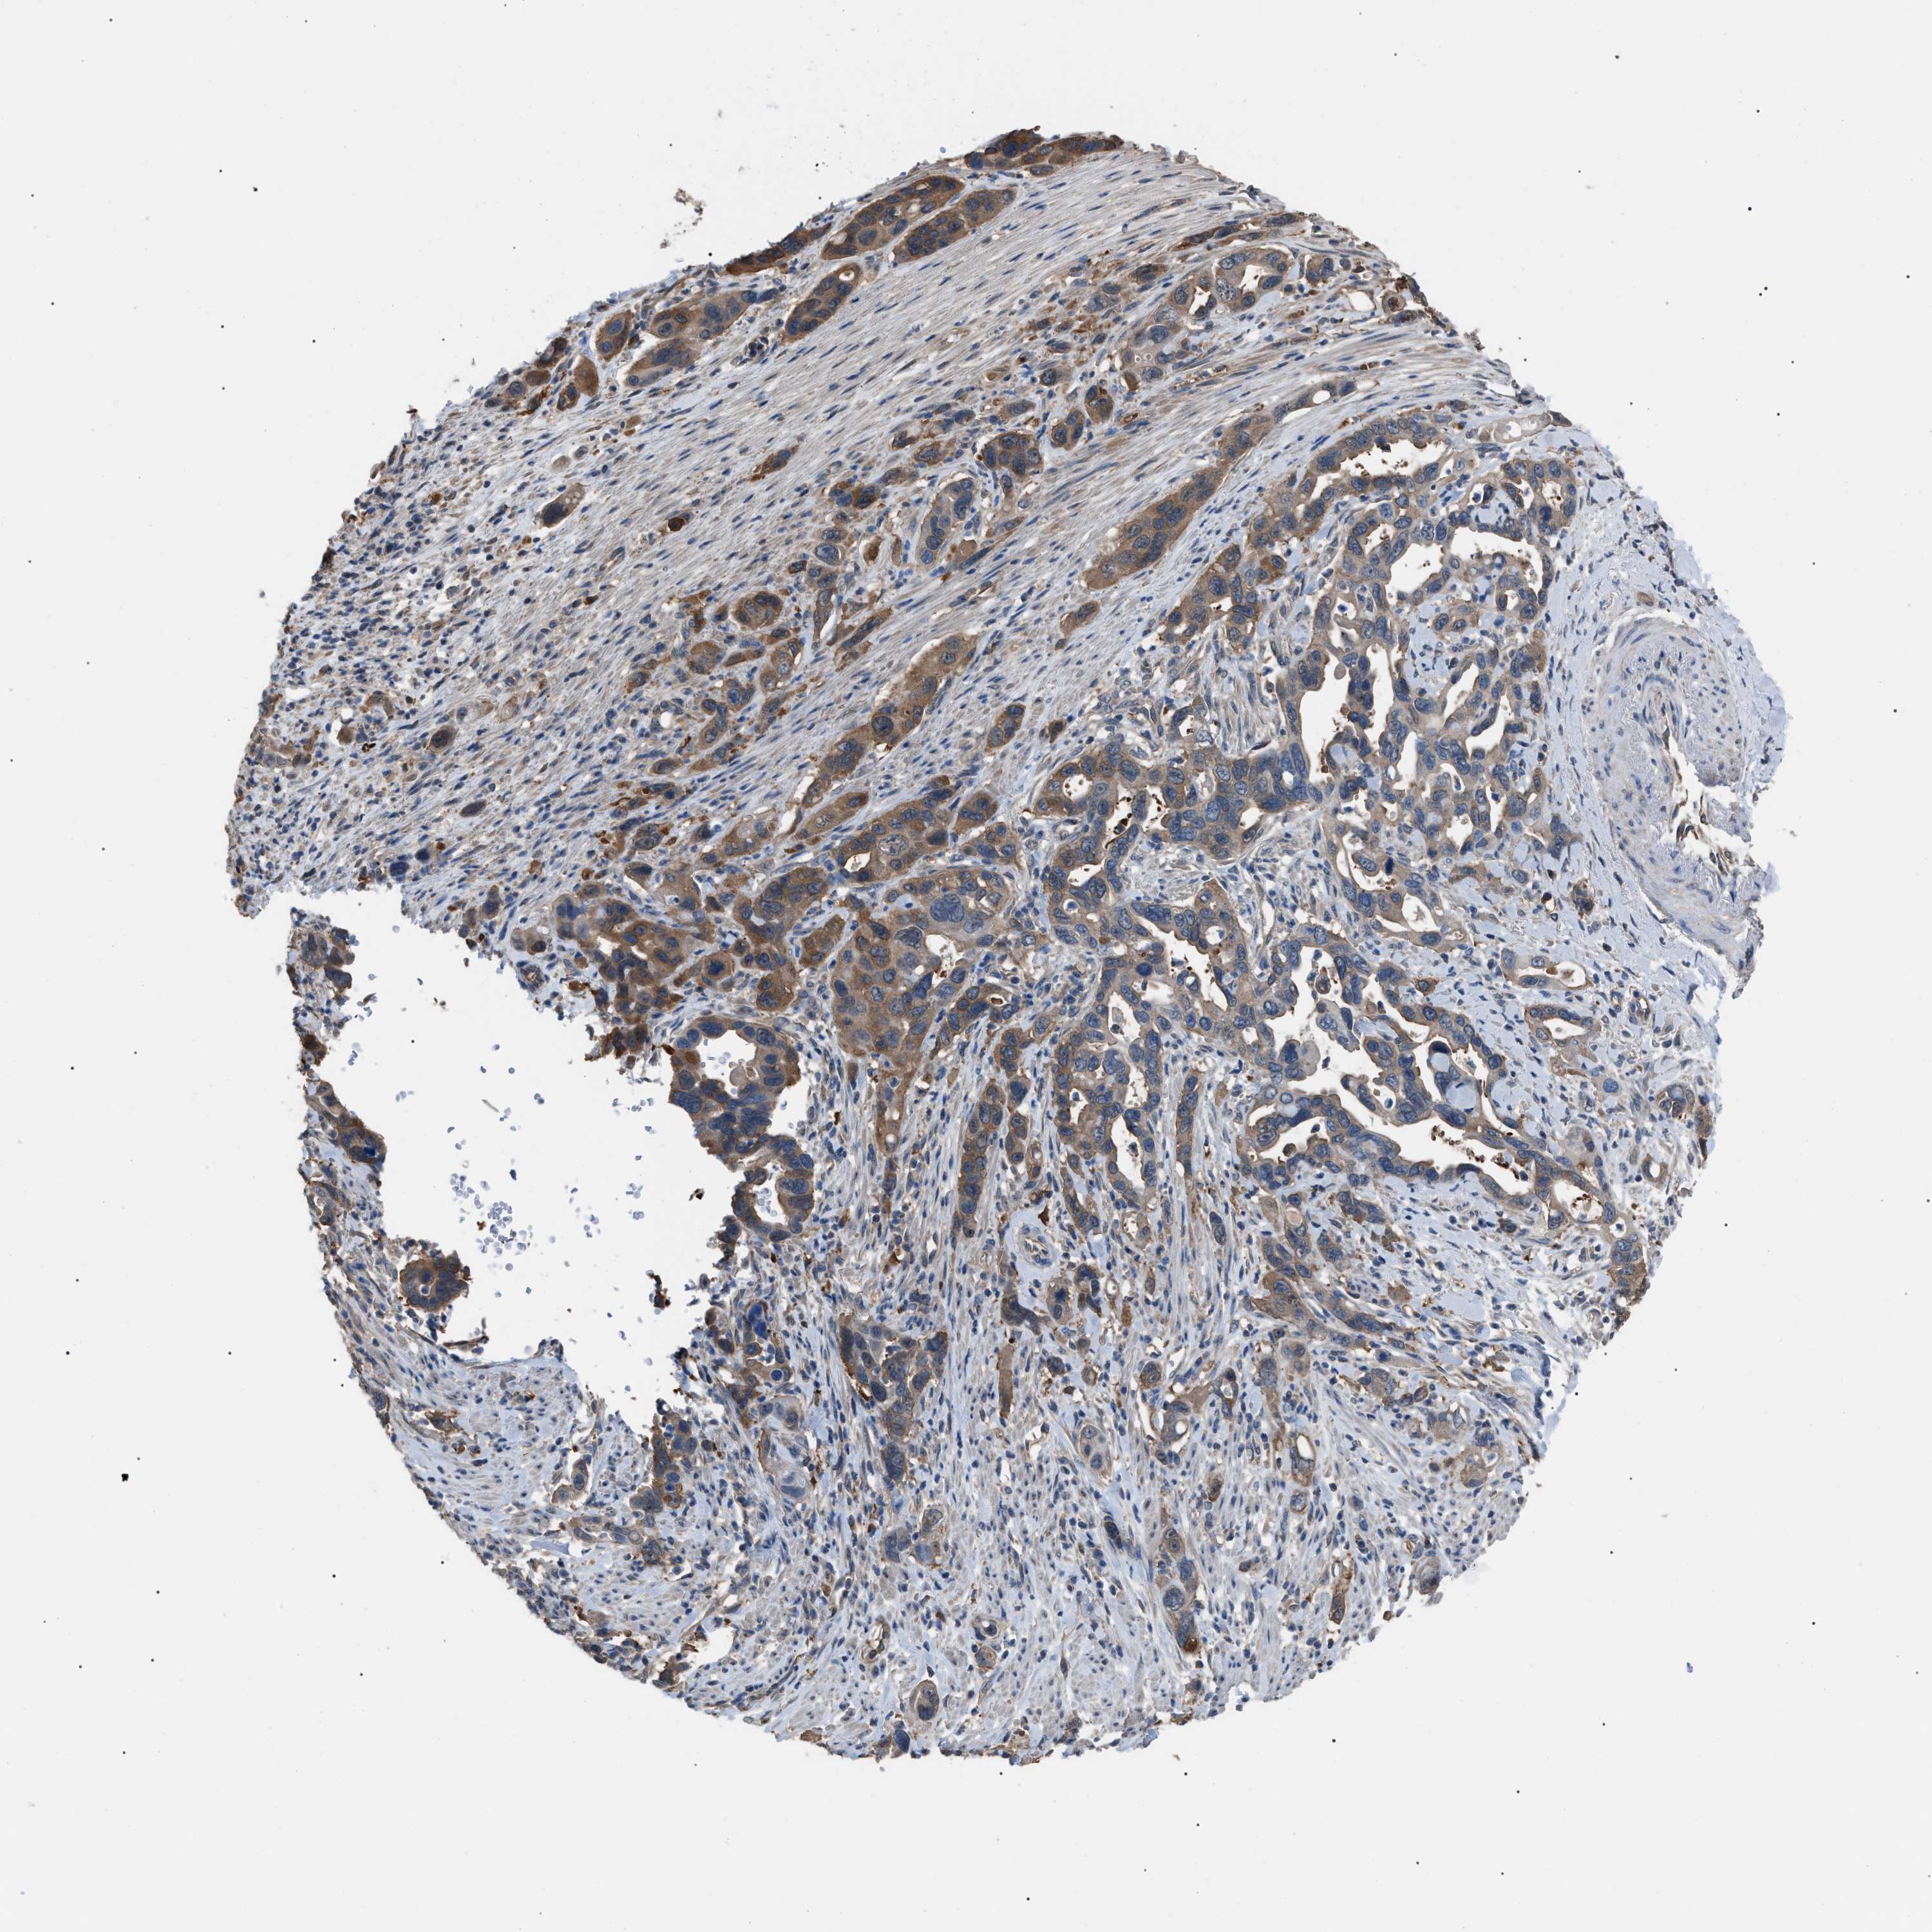

PANCREATIC CANCER - Protein expressioni

A mouse-over function shows sample information and annotation data. Click on an image to view it in a full screen mode. Samples can be filtered based on level of antibody staining by selecting one or several of the following categories: high, medium, low and not detected. The assay and annotation is described here.

Note that samples used for immunohistochemistry by the Human Protein Atlas do not correspond to samples in the TCGA dataset.

Antibody stainingi

Antibody staining in the annotated cell types in the current human tissue is reported as not detected, low, medium, or high, based on conventional immunohistochemistry profiling in selected tissues. This score is based on the combination of the staining intensity and fraction of stained cells.

Each image is clickable and will lead to virtual microscopy that enables deeper exploration of all samples and also displays staining intensity scores, fraction scores and subcellular localization as well as patient and tissue information for each sample.

Antibody HPA018471

Staining

High

Medium

Low

Not detected

Intensity

Strong

Moderate

Weak

Negative

Quantity

>75%

75%-25%

<25%

None

Location

Nuclear

Cytoplasmic/membranous

Cytoplasmic/membranous,nuclear

Adenocarcinoma, NOS